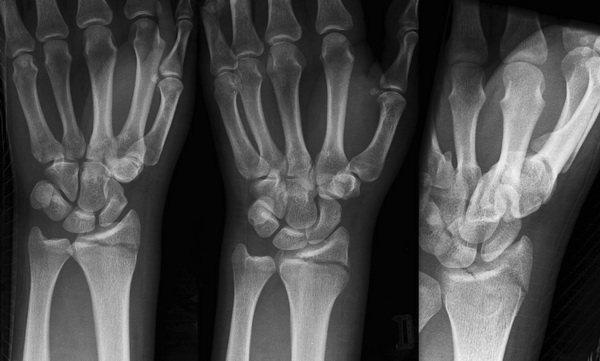

Диагностические мероприятия

При смещении шиловидного отростка лучевой кости необходимо провести следующие мероприятия:

- Сбор анамнеза.

- Осмотр врачом-травматологом.

- Рентгенологическое исследование в прямой и боковой проекции лучезапястного сустава.

- При необходимости возможно проведение таких дополнительных методов исследования, как, например, компьютерная томография (КТ) или ультразвуковое исследование мягких тканей (УЗИ).